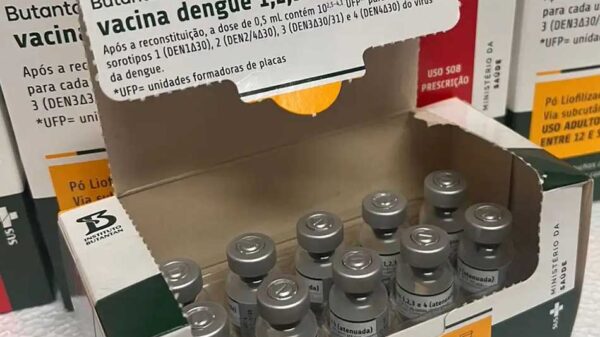

Foi identificado o caso de mais uma variante do novo coronavírus no Brasil. O Instituto Butantan informou que encontrou uma pessoa infectada com a subvariante denominada XE, que mistura duas modalidades da Ômicron.![]()

O caso foi confirmado pelo Ministério da Saúde, que divulgou nota anunciando que recebeu a notificação do Instituto Butantan. A pasta acrescentou que “mantém o constante monitoramento do cenário epidemiológico da covid-19”.

A variante XE é uma combinação de duas cepas diferentes da Ômicron: BA.1 e BA.2. O primeiro caso foi mapeado na cidade de Londres, em janeiro deste ano. Segundo o Instituto Butantan, a taxa de crescimento da XE é 10% superior à da cepa BA.2.

Contudo, o Instituto informa que ainda não há evidências suficientes acerca de mudanças, vantagens e desvantagens da circulação a nova variante em aspectos como gravidade, transmissão e eficácia de vacinas já existentes.